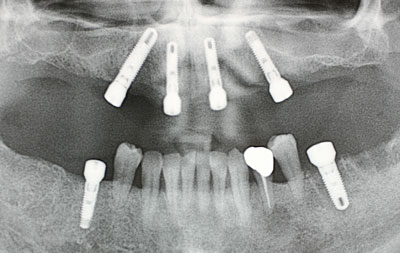

インプラント治療の進歩によって、上下顎ともインプラントを4本埋入(骨の中に植える)し、24時間以内にインプラント義歯を装着し、すぐに食べられるような治療が可能になりました。

下顎では以前から即時荷重を行って参りましたが、上顎では骨が柔らかく、さらに骨の量が足りない場合も多く、行っておりませんでした。しかし平成19年から上顎の即時荷重を開始し、平成23年3月まで50例以上行いましたが、脱落したインプラントは2本のみで、歯ぎしりをなさる患者様(1人で2本)でした。

本治療は4本埋入を基本としますが、骨の質が悪い場合、1-2本埋入本数は増加します。また即時荷重はインプラントがしっかり埋入できた場合のみ行える治療ですので、骨が柔らかい場合、即時荷重はできず、術後2か月ほどインプラントと骨の結合を待つ場合があります。